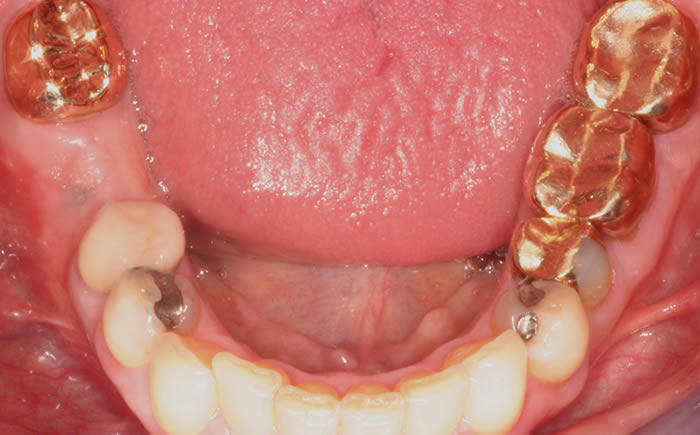

More back teeth replaced by dental implants

Case Three (2 images)